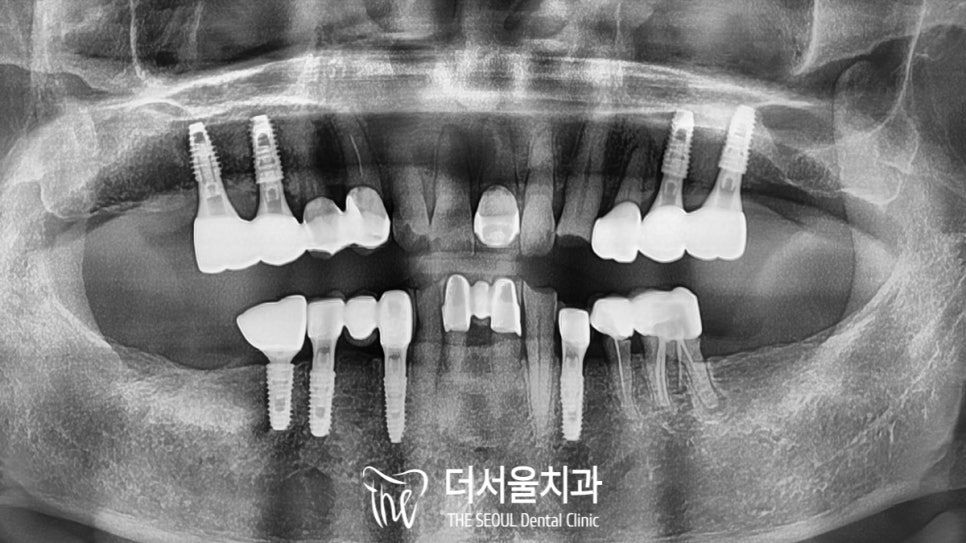

환자의 구강 내를 확인했더니..

틀니를 사용하고 계셨던 터라

꽤 많은 부분이 상실되어 있었습니다.

전체적으로 살펴봤을 때

치료를 받았던 흔적은 많이 보였으나..

연세에 비해 건강한 편이였습니다.

파노라마 사진에서 볼 수 있듯이

심하진 않지만 골소실이 나타나 있었는데요.

GBR을 동반하여

노인 임플란트 를 진행하는 것으로 계획을 세웠으며

본격적인 식립에 앞서 디지털 분석을 진행했습니다.